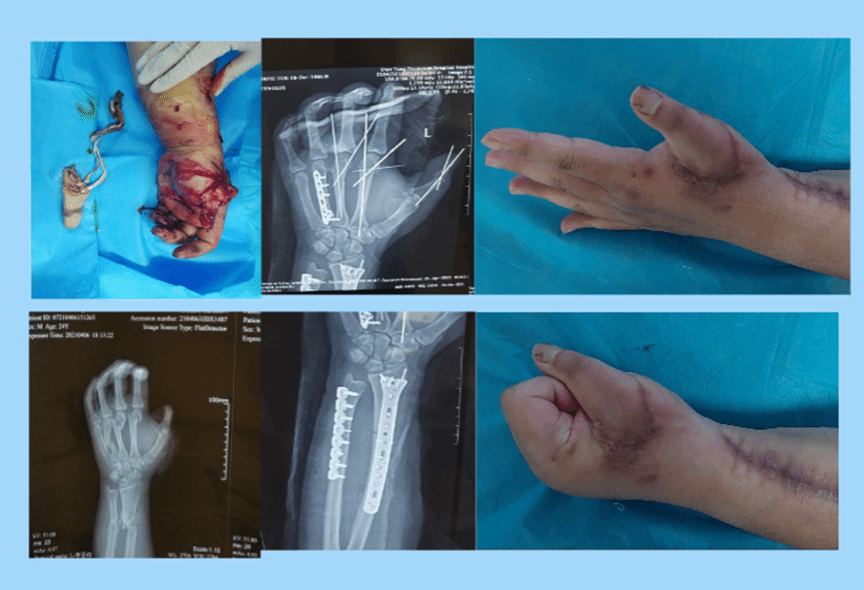

手外科医生不仅要恢复手外伤病人肢体(指体)的连续性,更要恢复手的功能。这样一位患者让马俊伟医生至今记忆犹新,“男性,23岁,右拇指撕脱离断,右手第二、三、四掌骨骨折,右侧尺桡骨粉碎骨折”,复杂的伤情,马俊伟医生与科室团队第一时间急诊手术使离断的指体再植成活后,二期又通过手术让所有的骨折得到了复位和固定、恢复了长度,由于术后密切的观察和及时处置,避免前臂骨筋膜室综合征的发生,手术非常成功。但这个时候患者找到了马俊伟医生,说:“马叔,我还年轻,虽然手术都成功了,我和家人都非常感谢,可是我们还是害怕将来手指不能活动、没有功能啊,我希望您能继续帮我做一做康复训练”,患者说的话也正是马俊伟医生一直思考的问题,不再停留于将残肢断臂接起来,而是希望利用循证医学证据和加速康复的理念让患者的功能尽可能恢复。于是从那天起,马俊伟医生就做起了这个患者的“私人康复师”,整个夏天只要一有时间,马俊伟医生都在帮助患者做康复训练,终于,功夫不负有心人,患者虽然伤情重且复杂,可是手功能却恢复的非常好,已经完全恢复正常的生活和工作。